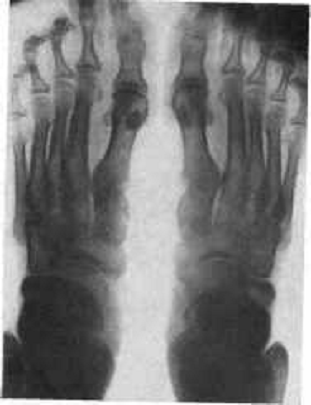

Рентгеновские снимки и их интерпретация